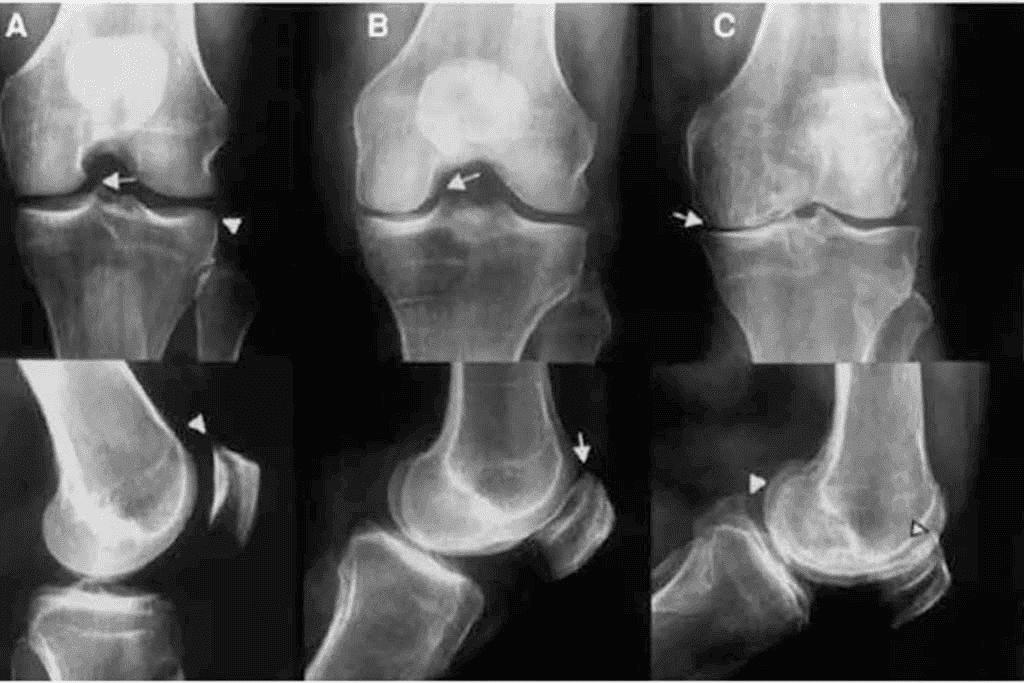

Osteoartritis Triplica Riesgo de Enfermedades Crónicas